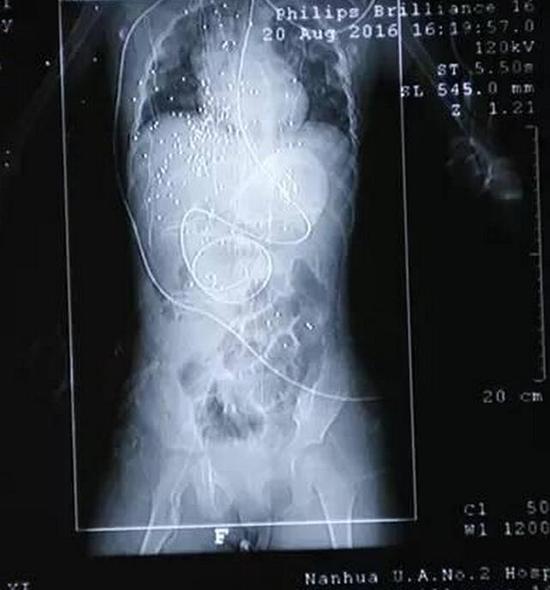

没有成功吓到这些人,刘鸣就开枪了,钢珠子弹全部打到了站在最前面的小西妹。小西妹的胸腔,腹部,胳膊,脖子,脸上都被钢珠打中。

小西妹受伤,舅舅周晨开车把小西妹送到了县人民医院。之后又转至南华大学附二医院,在医院输氧,输液处理之后,医生建议转到湘雅医院治疗。决定转院的时候,小西妹的血压持续下降,医生进行紧急手术,手术进行了4个小时。手术之后,小西妹情况不够稳定。

20日晚上,小西妹转到湘雅医院治疗。经过一系列治疗之后,医生表示,小西妹的生命体征已经趋于稳定。现在主要是防止感染和并发症。

目前,钢珠已经取出20多颗,但是还有一百多颗没有取出来。中南大学湘雅医院胸外ICU护师黄斌说,小女孩体内的钢珠有小黄豆大小,由于钢珠会活动,且比较小,如果进行手术的话,伤害可能会更大,如果没影响脏器的话,有些钢珠可以不用取。现在也担心钢珠会引起破伤风,医院正在做相关治疗。